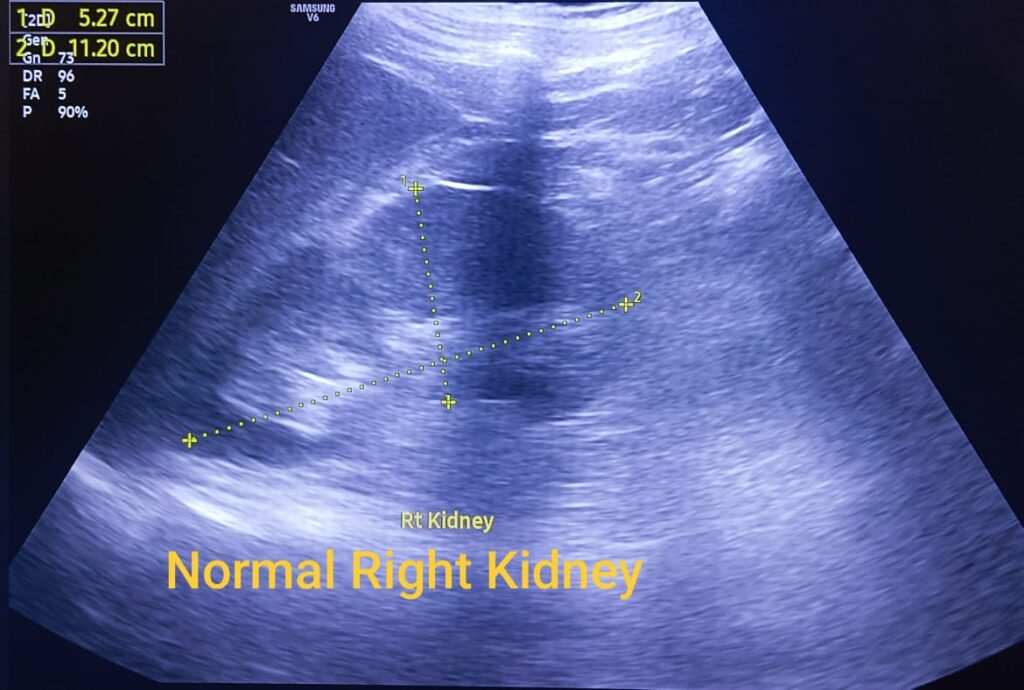

A boy aged approximately 21 years had complaints of pain abdomen. He appeared for ultrasound at Ardiss Imaging Centre, Greater Noida, one of the centres of excellence for such investigations.

Absence of a kidney shocked him. He was not ready for the news. His mother accompanied him, and she continued conversation multiple times to ensure that what was being conveyed was true.

In the evening, another case landed.

He was a 34 years old man and had developed dengue.

For him it was a news that a kidney was absent.